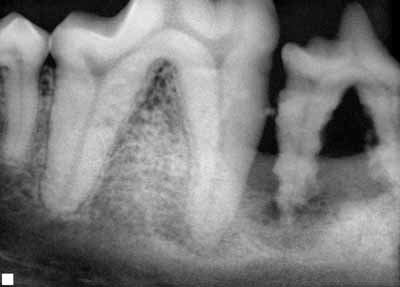

We can see the crowns of our pets' teeth and can see how much tartar is on them. While the tartar accumulation may be ugly, it is not these deposits that are the main problem. The plaque and tartar below the gum line is the most significant concern. Unfortunately, we cannot see how much of those deposits there are. We also cannot see how much tissue damage has occurred causing abnormal pockets of infection and how much bone loss there might be.

We must get your pet under general anesthesia so that we can probe, explore, and examine below the gum line around each tooth. We also need to get intra-oral dental radiographs to evaluate the bone and root structures. Dental radiology is absolutely essential! Radiographs are taken to assess the teeth roots and the bone supporting them. Radiographs are a must to see what is going on inside and around the roots. Only by doing a thorough, detailed examination can we arrive at an accurate assessment of your pet's periodontal condition. We need this detailed evaluation to develop the appropriate treatment plan for your pet.